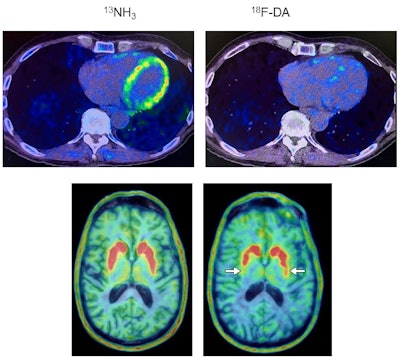

Heart and brain PET scans from a study participant who developed Parkinson’s disease support a “body first” progression. The top pair of PET scan images show low F-18 dopamine-derived radioactivity in the heart (right, with N-13 ammonia PET scan on left). Later, brain scans showed a loss of dopamine-producing neurons and the individual developed symptoms of the disease. Image courtesy of the National Institutes of Health.